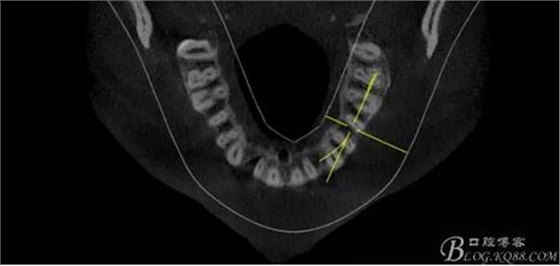

(1)檢查:12唇側(cè)牙齦可見竇道,牙體顏色較鄰牙暗,無光澤,形態(tài)完整無缺損,唇側(cè)及近遠(yuǎn)中向未提及牙周袋。腭側(cè)齦緣輕度紅腫,舌側(cè)窩可探及裂溝,可見浸墨狀痕跡,沿裂溝舌側(cè)探診牙周袋深大于11mm,除患牙外全口牙周狀況良好,為探及牙周袋,牙齦色粉紅。邊緣菲薄,質(zhì)地堅韌。12冷熱診無反應(yīng),叩診(+-),無明顯松動,無咬合創(chuàng)傷。12根尖x線片示,根管中三分之一中可見一斜向線樣透射影像根尖區(qū)及遠(yuǎn)中根三分之一可見低密度透射暗影,錐形束CT示12根尖區(qū)唇腭向骨吸收已穿通,根面溝達(dá)根中三分之一卷曲分出另一牙根,再未見其他明顯的根管系統(tǒng)。